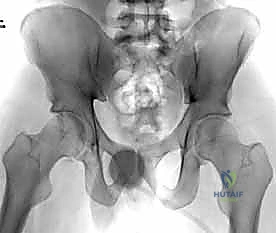

عند حدوث قوة قاهرة تفوق قدرة تحمل هذه الأربطة، يتمزق المفصل وتنفصل عظام العانة عن بعضها، وهو ما يُعرف طبياً بـ "كسر الكتاب المفتوح" (Open Book Fracture) إذا تجاوز الانفصال 2.5 سم. هذا الانفصال يؤدي إلى عدم استقرار كامل في الحلقة الحوضية.

| دواعي الاستعمال | انفصال أقل من 2.5 سم، حلقة حوضية مستقرة، المريض غير قادر على تحمل التخدير. | انفصال أكبر من 2.5 سم (كسر الكتاب المفتوح)، عدم استقرار الحوض، إصابات متعددة. |

يتم تقييم المريض بشكل شامل (أشعة سينية، أشعة مقطعية ثلاثية الأبعاد) لتحديد حجم الإصابة بدقة. تُجرى العملية تحت التخدير العام لضمان استرخاء العضلات بالكامل وعدم شعور المريض بأي ألم. يتم وضع المريض على ظهره على طاولة العمليات، وتُعقم منطقة البطن والحوض بالكامل.